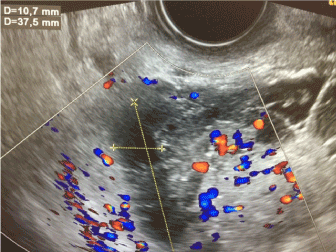

Bilateral adnexal hydatidosis in primary infertility. Unilateral pelvic pain, pain during middle of menstrual cycle (mittelschmerz). Possible causes include pelvic inflammatory disease.

.abdominal tenderness, bilateral adnexal tenderness, or cervical motion tenderness (cmt).

À des douleurs abdominales dues à une lésion par écrasement. Check the full list of possible causes and conditions now! If you are experiencing adnexal tenderness it may be due to cysts or ectopic. The absence of cervical motion, uterine or adnexal tenderness makes the diagnosis unlikely.